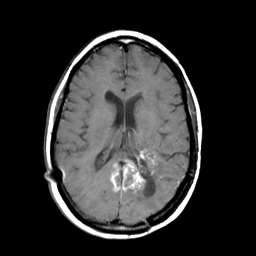

MR Study #3 -- Slice #31

Tour 1: Next/Previous/Start: The inferior extent of the lesion is seen to involve the left medial occipital lobe at this level, and to extend to the right side as well, probably along fiber tracts in the splenium of the corpus callosum.